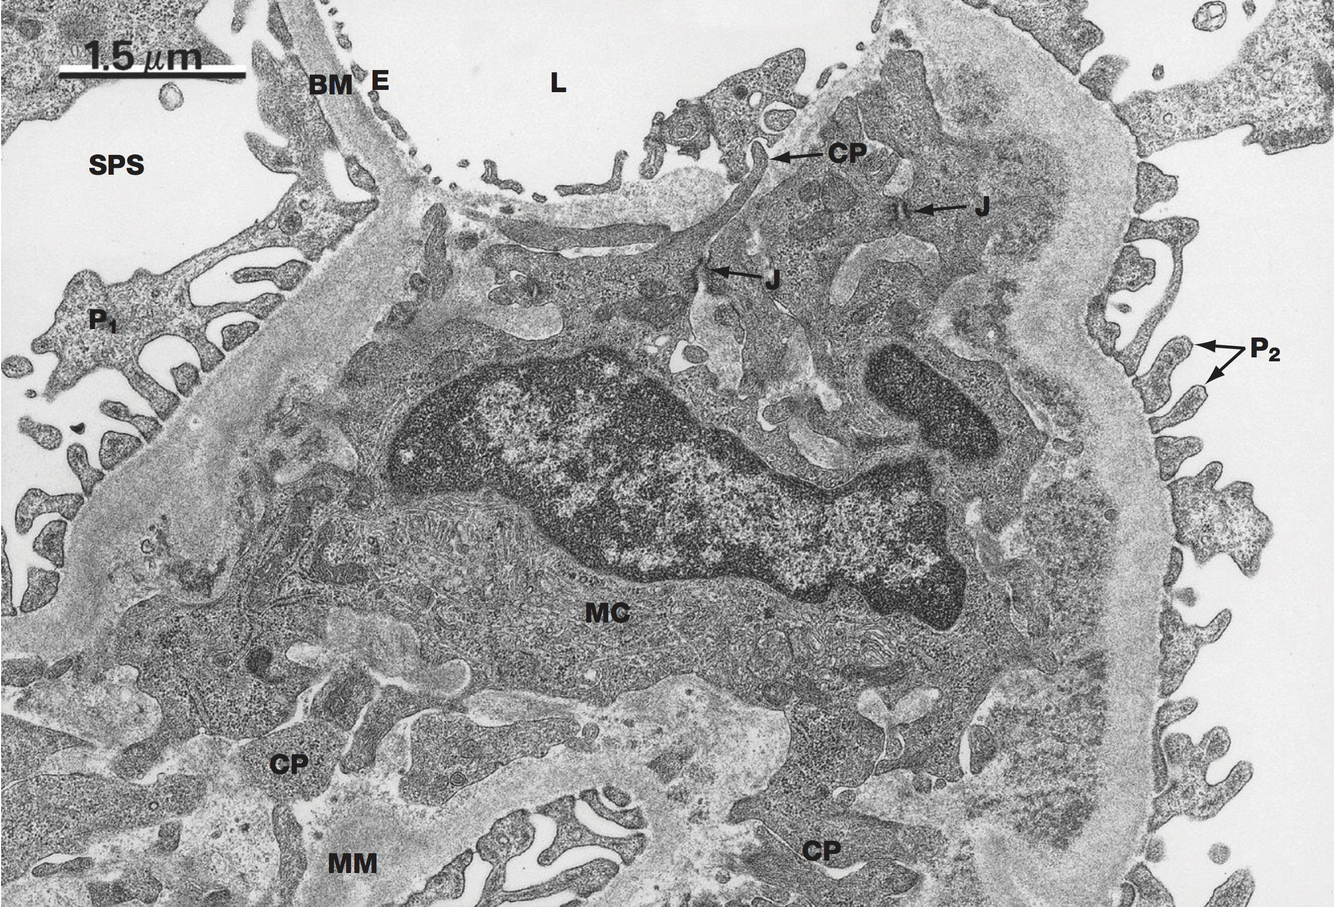

Juxtaglomerular Apparatus

Includes: